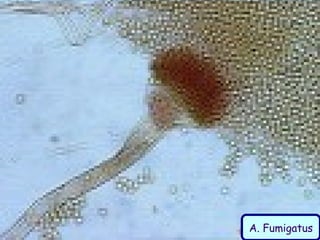

STRUCTURE

Mycélium (hyphes) formé de filaments de taille

régulière, de 4µm de diamètre, avec des ramifications

dichotomiques à angle aigu.

Filaments dits conidiophores (stipes) se terminant par

une vésicule de forme globuleuse sphérique de taille

variable.

Autour de la vésicule, sont disposées une ou plusieurs

rangées de phialides, à l’intérieur desquelles naissent

des spores ou phialospores.

Phialides sont pfs portées par des métules et

recouvrent tte vésicule ou seulmt la partie sup.

L’ensemble : tête aspergillaire.

   Chaque tête peut relarguer jusqu’à 10 spores.

A. Fumigatus

 A. fumigatus :

Croissance très rapide à 37°C, possible à 50°C.

Colonies blanches à vertes, puis d’un vert foncé à gris

noirâtre.

Vésicule en massue.

Phialides directement portées par vésicule (unisériées),

présentes sur les 2/3 du sommet.

Conidies rondes vertes et échinulées de 2,5 à 3 µ de

diamètre. Elles sont en chaînettes et parallèles à l’axe

du conidiophore.